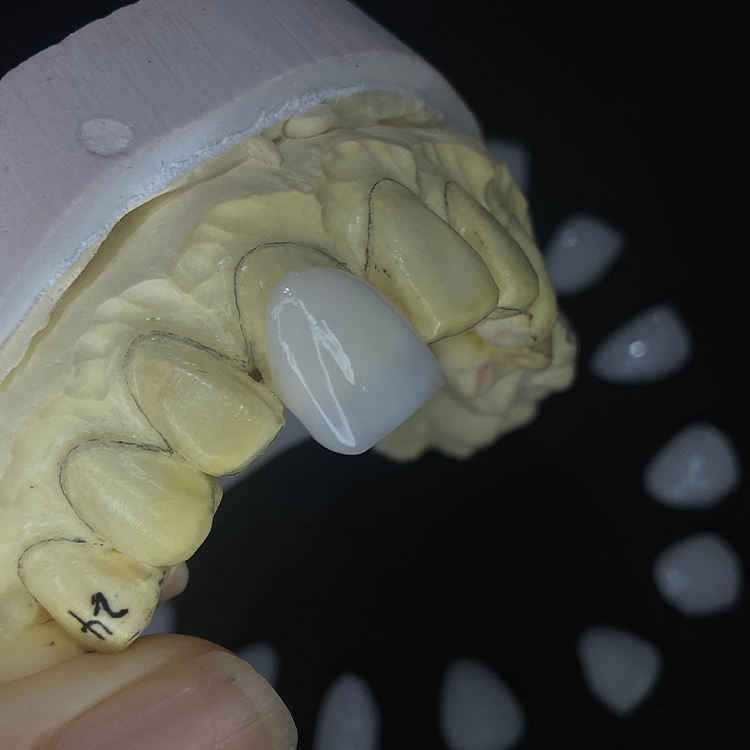

A full E.max veneer is monolithic lithium disilicate, usually finished with stain, glaze, gloss control, and surface texture rather than with an added veneering porcelain layer, which is why labs sell it as the more repeatable route for multi-unit smile cases where fit, value control, and cross-unit consistency matter more than showing off a ceramist’s incisal magic. That is also why I tend to trust it more when the doctor wants canine-to-canine discipline, not a single hero central incisor.

A layered E.max veneer starts with a lithium disilicate core and then adds porcelain layering to build depth, translucency gradients, halo effects, and surface texture, which is exactly why it can look outstanding in high-end anterior work and exactly why it becomes less forgiving when the prep space is inconsistent, the stump shade is sloppy, or the photos are weak. Beautiful? Absolutely. Automatic? Not even close.

A 2025 long-term veneer survival study found a cumulative 15-year survival rate of 96%, but it also found that teeth with dentin exposure had higher failure risk, with an odds ratio of 3.47 when dentin exposure exceeded 30%. That is the part too many cosmetic pitches skip. Not sexy enough, I guess. But it is the real part. Prep design still runs this business.

The same logic shows up in the site’s E.max crowns page, which also emphasizes translucency, anatomy, and fit consistency. Material quality matters. But prescription quality, photos, reduction notes, and stump shade still decide whether the case ends in applause or a remake bag.

Full E.max veneers are generally the safer mechanical bet because the monolithic design removes the extra veneering layer that can add more interfaces and more opportunities for chipping or fracture-related complications, although actual survival still depends heavily on enamel preservation, bonding quality, occlusion, and disciplined case selection. That is why I call it the lower-drama option, not the magic option.

Layered E.max veneers can look more natural in elite anterior cases because the ceramist can control translucency gradients, halo, warmth, and surface texture more aggressively, but they are not automatically better-looking when prep space, stump shade, cement shade, and photo communication are weak or inconsistent. In other words, artistry without control is just expensive hope.